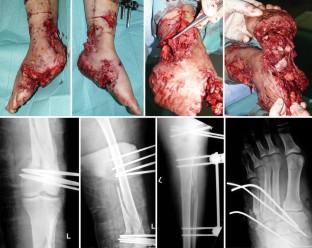

This article reports the case of a 23-year-old woman who sustained severe soft tissue injuries with open fractures of the left distal femur, the left proximal tibia, a subtotal amputation of the left foot with injuries to the anterior and posterior tibial artery due to a bomb blast. When the patient was transferred to our hospital 17 days after the trauma, all primarily closed wounds were severely infected. The fractures were treated by external fixateur and k-wire fixation. After debridement and initiation of negative pressure therapy the anterior tibial artery was reconstructed after 3 days and partial wound closure by a rectus abdominis muscle flap was achieved after 19 days. After almost total wound closure was accomplished open reduction internal fixation (ORIF) was performed for the distal femur fracture and a modification of the external fixateur for the tibial and foot fractures. The negative pressure therapy is an important component for treatment of complex soft tissue injuries and open fractures; however, it must be embedded in an interdisciplinary treatment plan with well-defined treatment goals.

Abb. 1